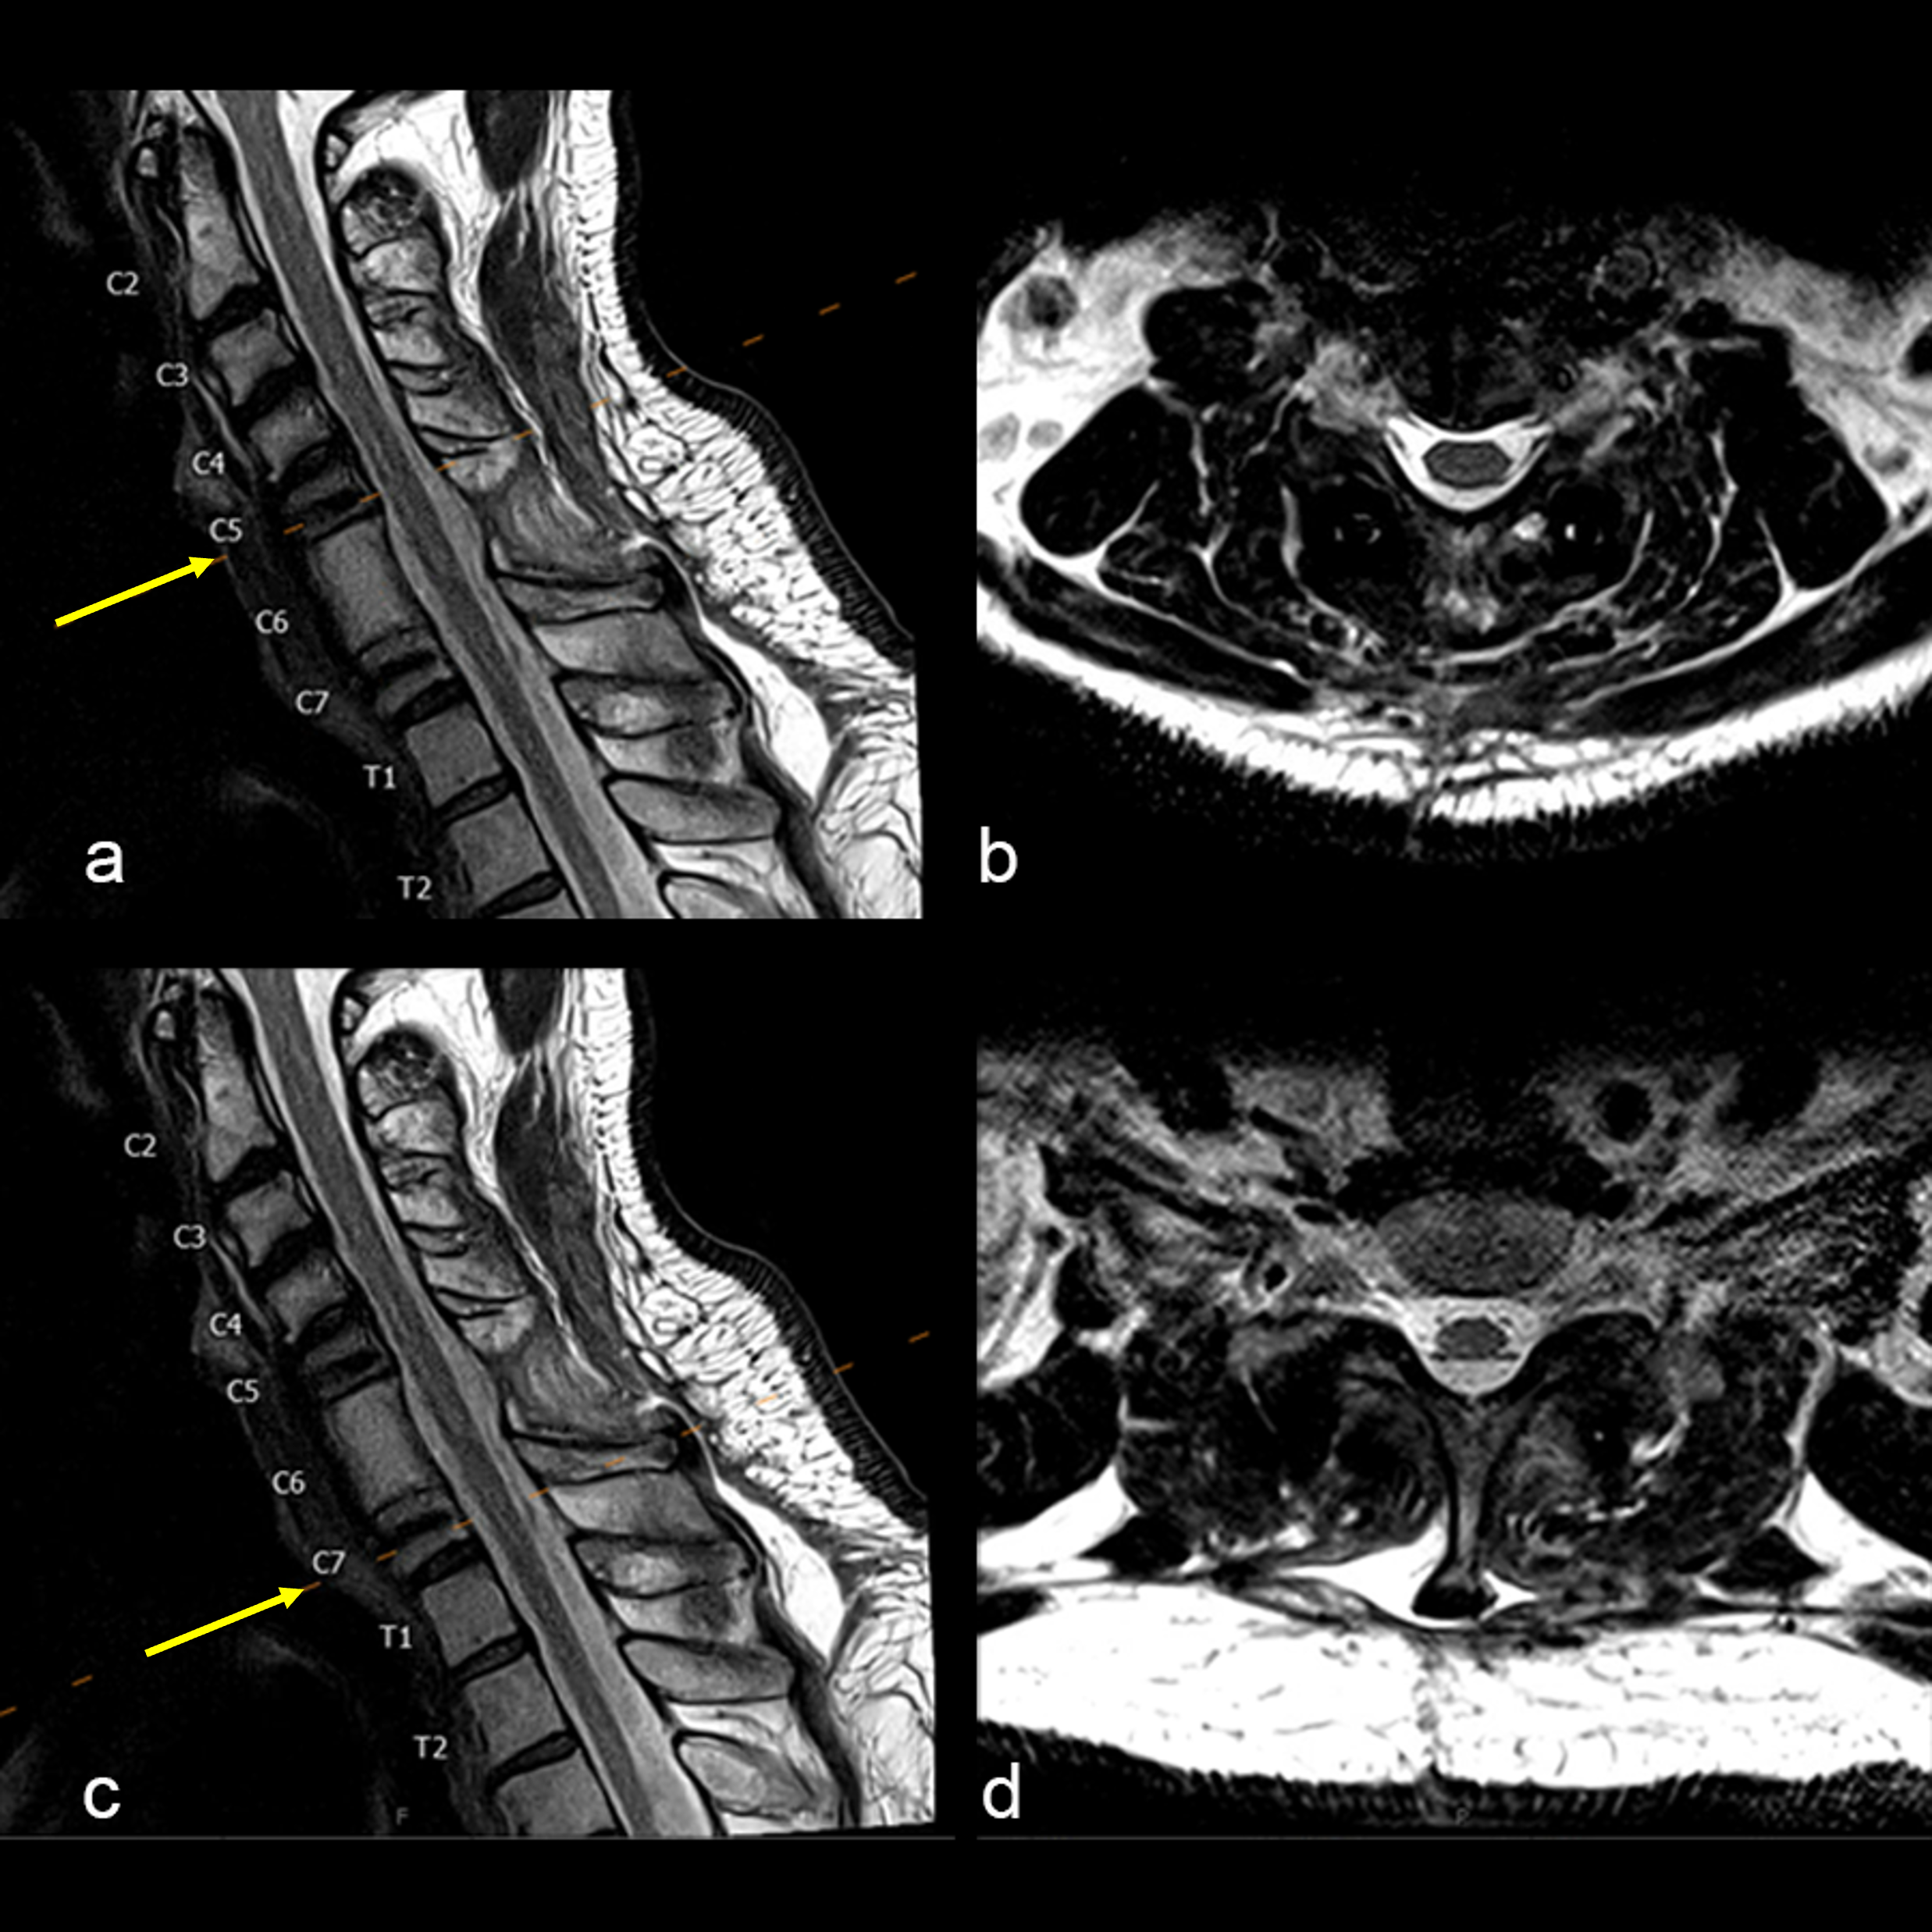

A 47-year-old male presented with neck pain. Upon examination, he was neurologically intact. He underwent an MRI of the cervical spine that demonstrated a non-enhancing T1-hypointense and T2-hyperintense lesion (Fig 1).

The patient underwent a CT guided biopsy that demonstrated a brachyury positive lesion consistent with a chordoma versus benign notochordal tumor. He underwent a two-stage operation for en bloc resection of the lesion. Cervical spine stabilization was achieved using CMORE® Carbon/PEEK implants. The radiolucent nature of these implants permits artifact-free postoperative imaging and more precise radiation treatment, an important consideration in patients with spinal tumors.

The anterior cervical spine was reconstructed from C5-C7 using tricortical iliac crest autograft and an icotec Carbon/PEEK anterior cervical plate system (Fig 4). Following reconstruction, imaging (Fig 5) demonstrated no MRI artifact in the sagittal (a,c) and axial (b,d) planes.